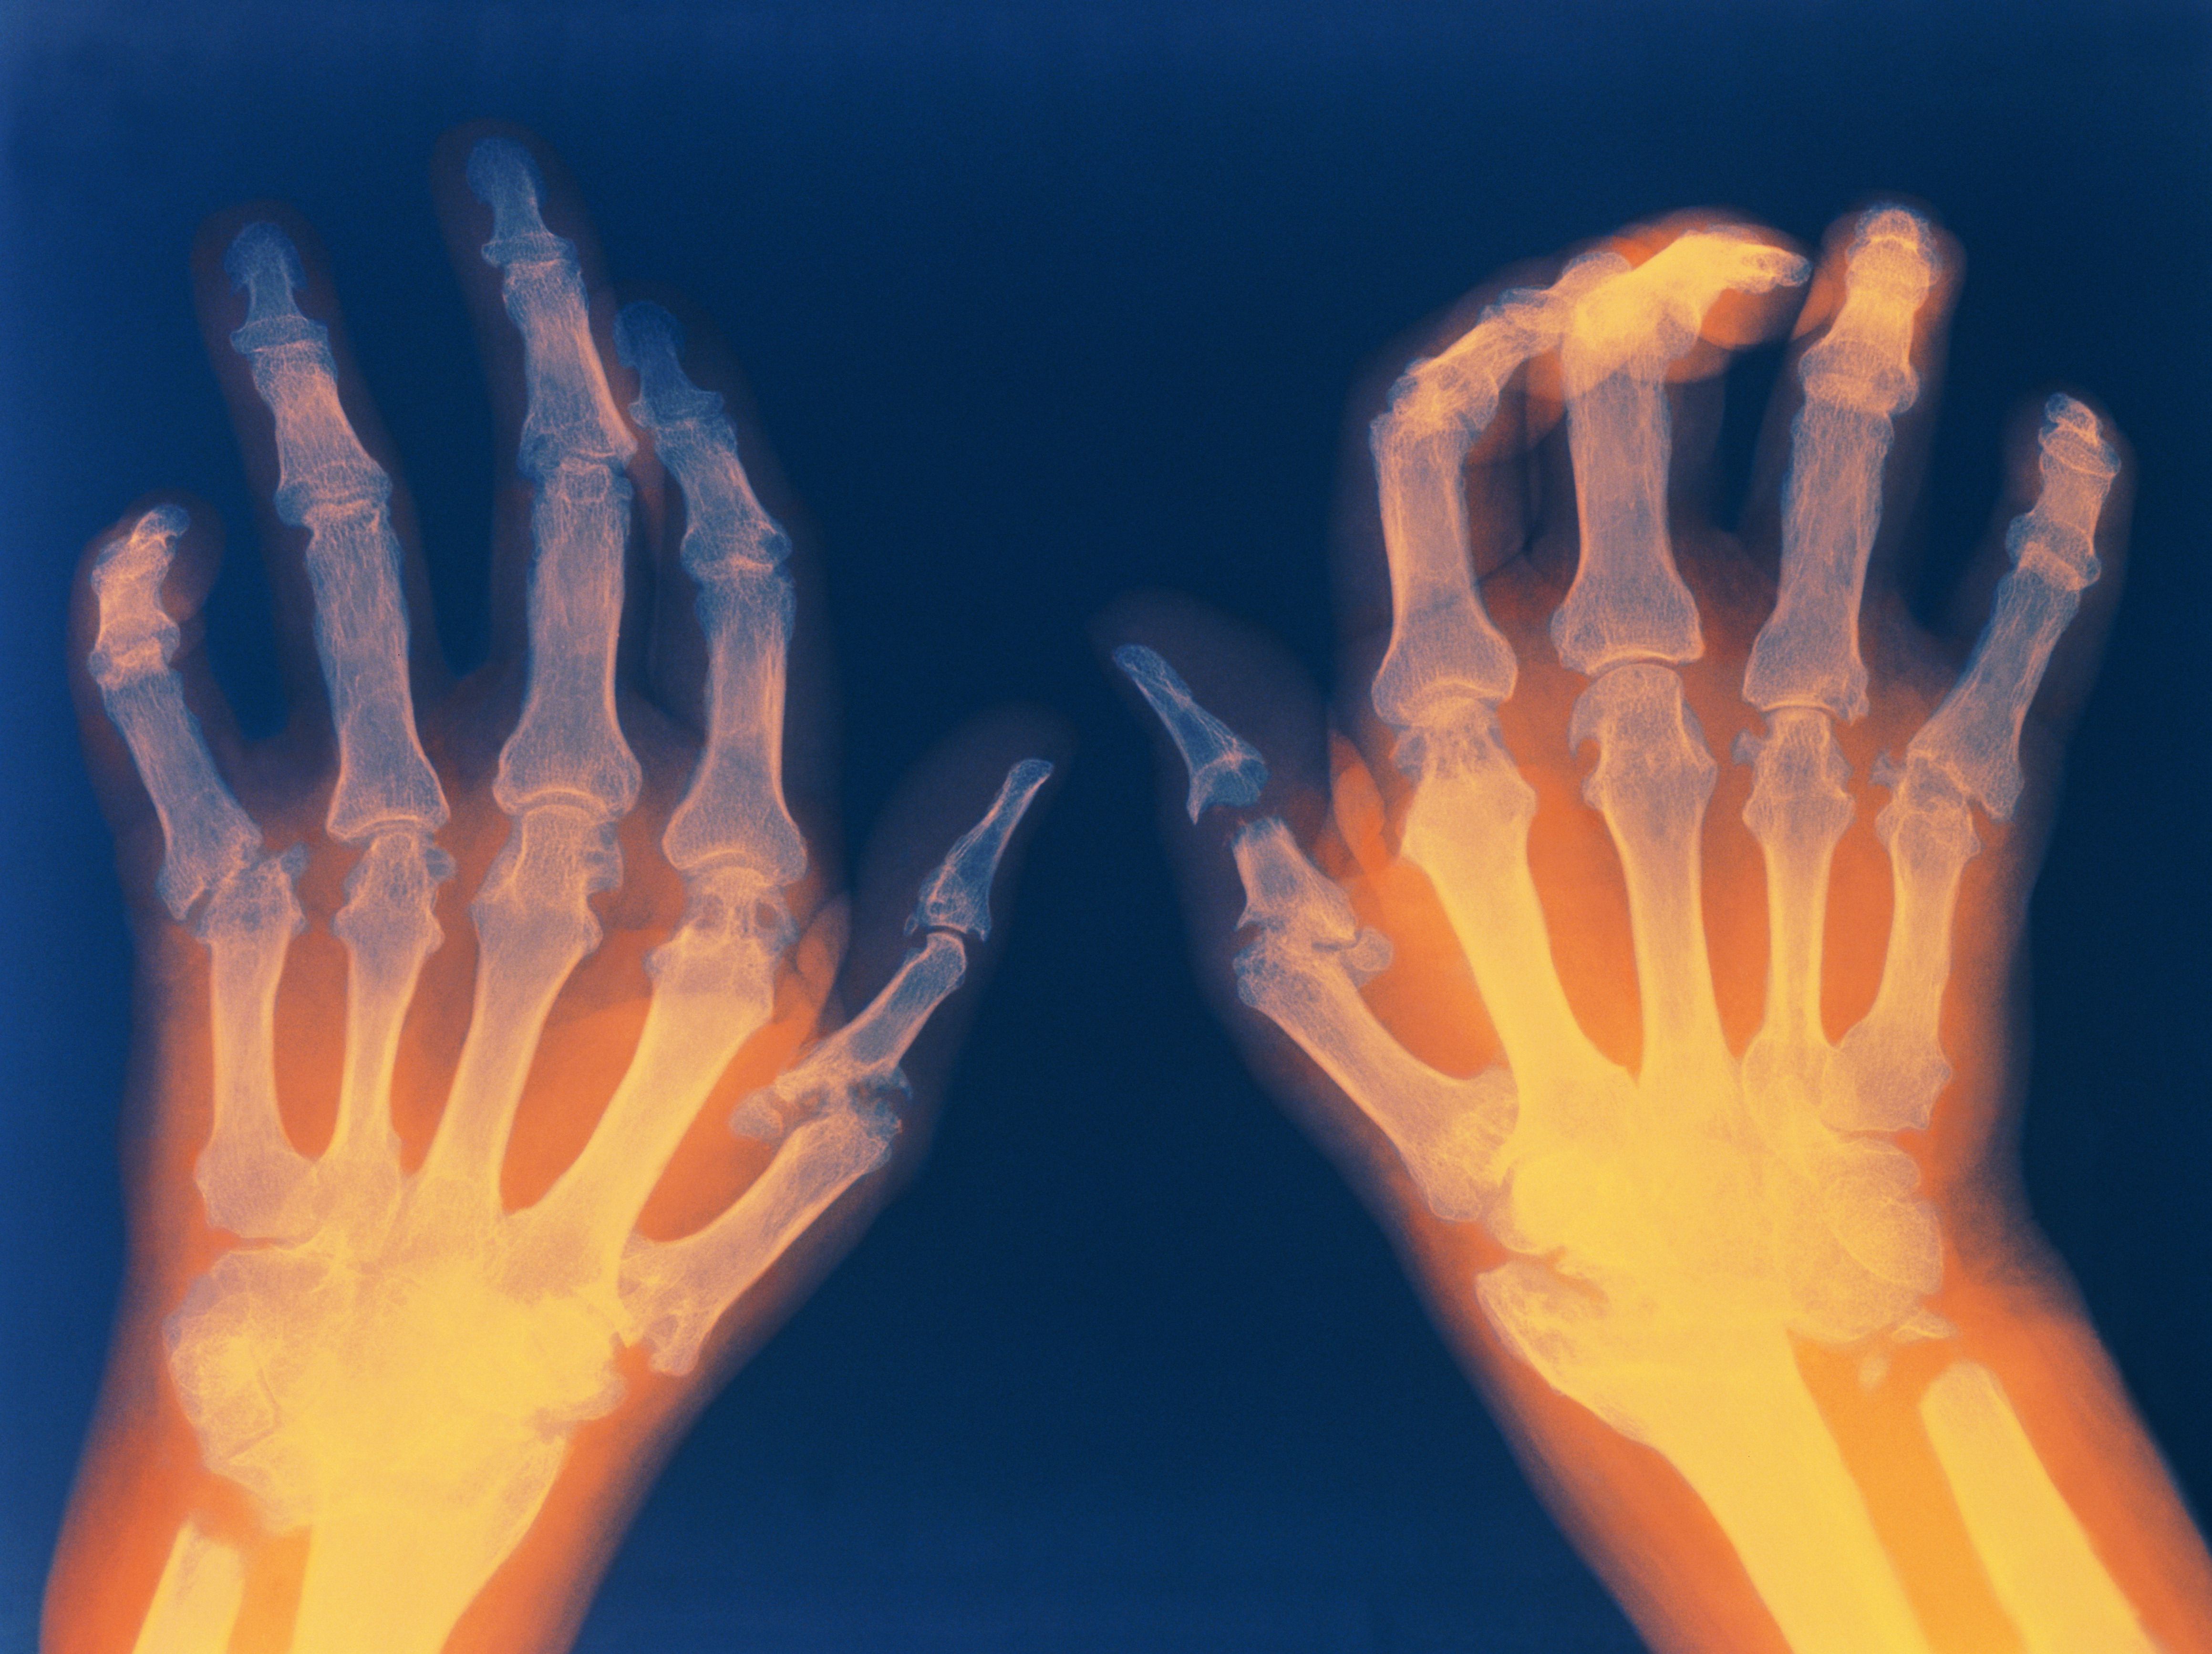

Σε τελική ανάλυση, αυτό που είπε ο Pigou είναι απλό: καλό το Αόρατο Χέρι, αλλά πολλές φορές παθαίνει αρθρίτιδα και αποτυγχάνει στο λεπτεπίλεπτο έργο του. Ο Milton Friedman πρέπει να έβλεπε πολλά όνειρα με σκληρωτικά αόρατα χέρια να τον δέρνουν.